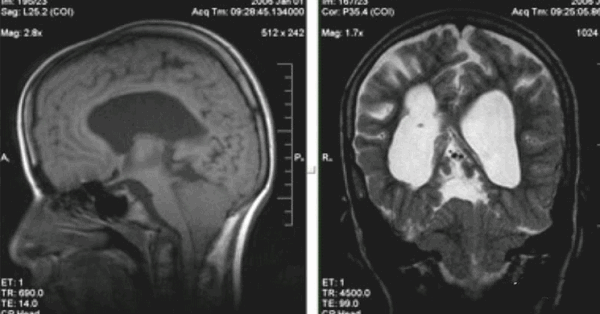

Синдром Арнольда-Киари (смещение миндалины мозжечка ниже границ большого затылочного отверстия)

МРТ показывает миндалины мозжечка, расположенные на границе большого затылочного отверстия. У детей в возрасте 5-15 лет возможно каудальное смещение анатомического образования в позвоночный канал (в норме не более 5 мм).